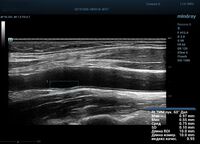

Для более искушенных в результате исследования существует качественно новый уровень измерения комплекса интима-медиа. Система RIMT использует нативные акустические данные (RF-Data) и проводит несколько измерений в режиме реального времени, получая измерения IMT с точностью до 5 мкм. Измерения проводятся в течении шести сердечных циклов, таким образом резко снижается вероятность погрешности.